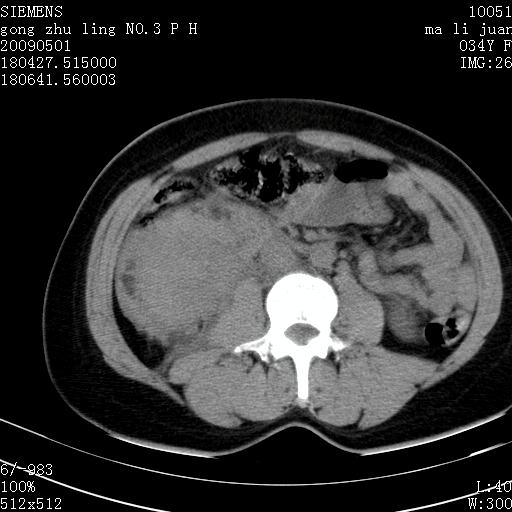

标题: CT19733:右肾碎裂

青年女性,骑摩托车摔伤。

右肾碎裂伤,包膜下血肿。

术中仅见右肾碎裂,肾蒂血管未见断裂。

支持 右肾破裂伴肾包膜下及肾周血肿。

右肾破裂并右侧腹膜后间隙出血。